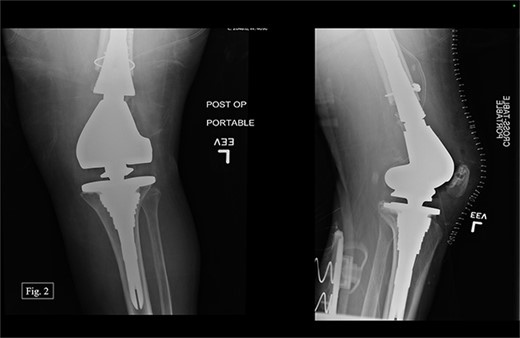

The previous medial parapatellar approach was used to identify and shell out the fractured DF with an arthroplasty component end block. Press fit trials were used, and the contralateral knee joint height was compared. We used the DePuy Synthes MBT revision metaphyseal sleeve, tibial tray rotating platform, MBT revision cemented, limb preservation system (LPS) tibial insert hinge, LPS distal femoral component, LPS sleeve adapter to distal femoral component, universal femoral sleeve, and a universal fluted stem. The patient experienced 1000 mL of intraoperative blood loss, awoke without incident, and was admitted to the ICU for monitoring and management. Postoperative anterior–posterior (AP) and lateral X-rays were taken (Fig. 2).